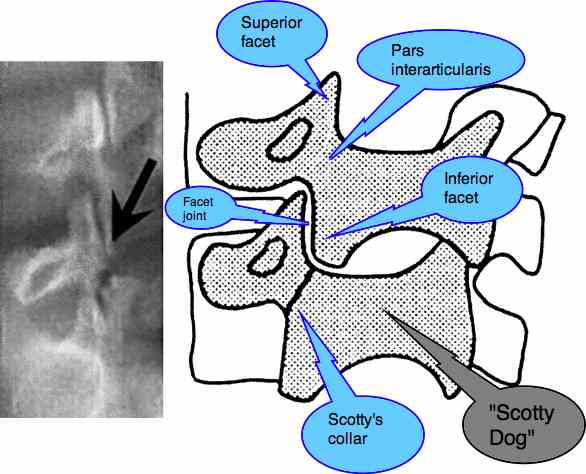

This fracture is called a "spondylo-lysis". It occurs through the so-called "pars inter-articularis", that narrow isthmus of bone that lies between (inter) the two articulating facets, one superior, and the other inferior.

Each vertebra has two inferior facets that articulate with the two superior facets of the vertebra below it. Notice the locking mechanism: the inferior facet of the vertebra above locks onto the superior facet of the vertebra below preventing any possibility of a forward slip. Unless...

Does Scotty have a collar?

On an oblique X-ray, the clinician is always asking the question, "Does Scotty have a collar?" Can you visualise the Scotty Dog? Between his ear (the superior facet) and his front leg (the inferior facet) lies the narrow isthmus of bone that is prone to fracture in the young child. This is known as "spondylolysis".